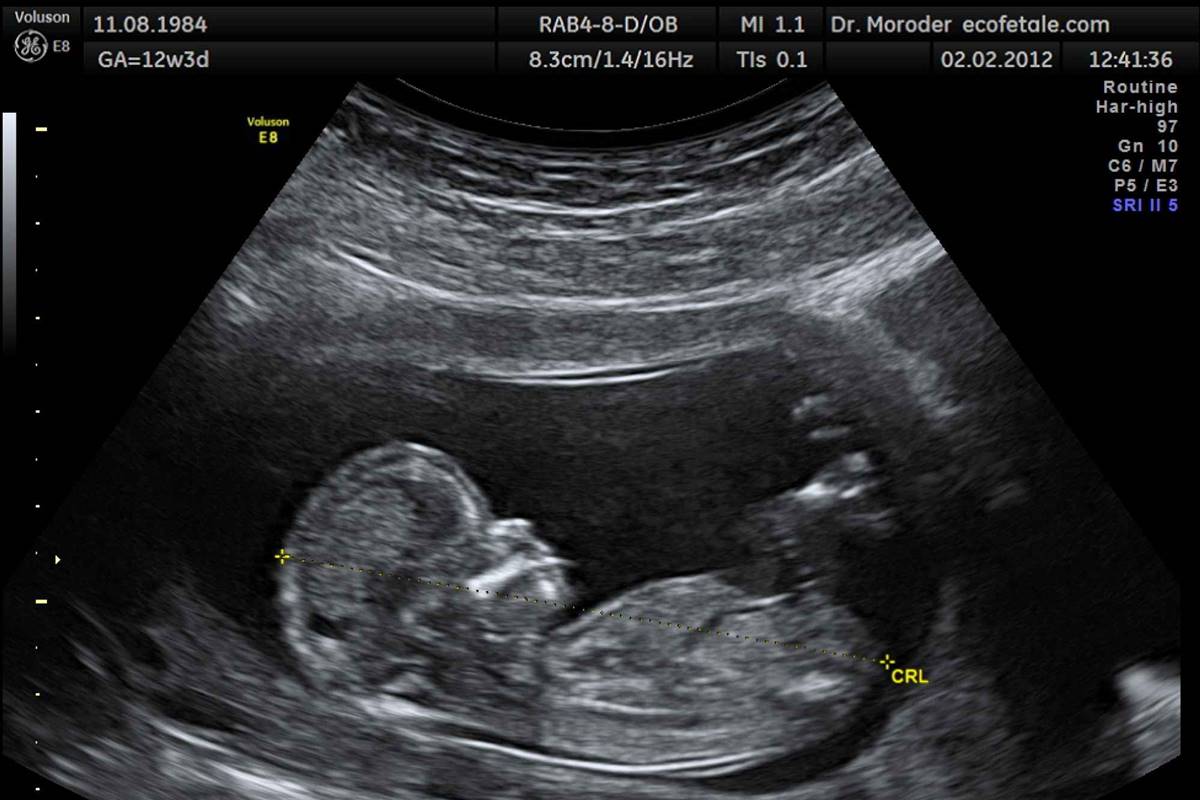

O experimento foi realizado em mulheres grávidas entre 14ª e 39ª semana de gravidez. Ao longo do estudo, a equipe utilizou um ultrassom para observar a reação dos fetos depois de ouvir uma música.

O exame de ultrassonografia realizado antes de iniciar a música mostrou que cerca de 45% dos fetos fizeram momentos com a cabeça e membros de forma espontânea, enquanto 30% movimentou a boca ou língua, e 10% colocou a língua pra fora.

Depois de expostos ao som emitido através do dispositivo intravaginal, 87% dos fetos reagiram com movimentos da cabeça e dos membros e pararam de se movimentar quando a música foi interrompida.

Além disso, 50% dos fetos reagiram com um movimento impressionante, abrindo bastante sua mandíbula no ritmo da música e colocando a língua para fora o máximo possível.